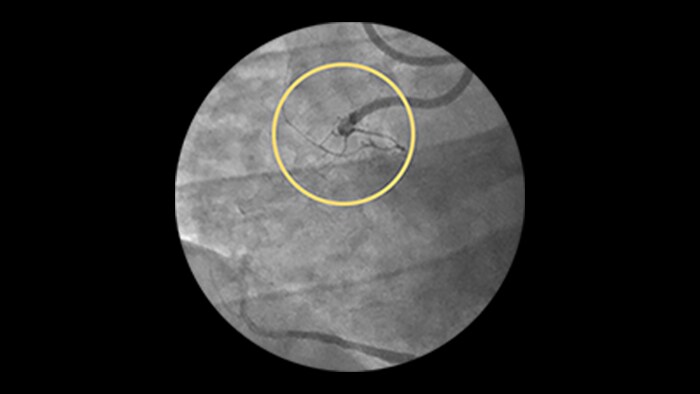

Diffuse Disease

Approximately 20% of the coronary lesions treated today are long and diffuse.1,2

Clinical challenges

– Stent length is an independent predictor of in-stent restenosis and thrombosis.

– Stenting long segments with multiple and or overlapping stents may lead to injury to the vessel wall integrity.

– Diffuse CAD may be underestimated by evaluation with coronary angiography.

– Determining reference vessel sizing can be challenging when the vessel is diffusely diseased.

IVUS-guided vs. angiography-guided outcomes3

Advanced tools for optimal PCI outcomes